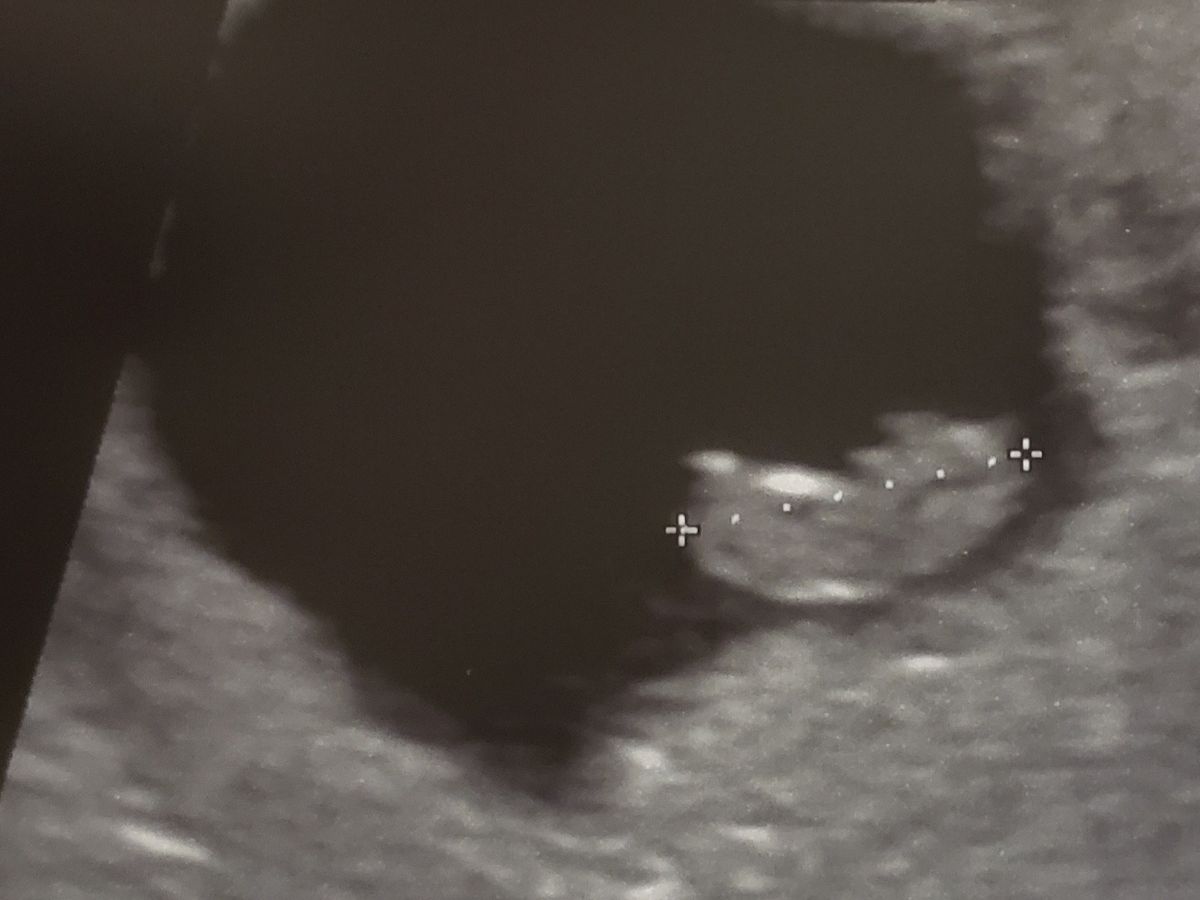

confirmation today. I got the horrible news at my last ultrasound on 5/26/22.

My baby stopped growing and its heart

stopped beating. My body hasn't released the baby on its own yet and hasn't